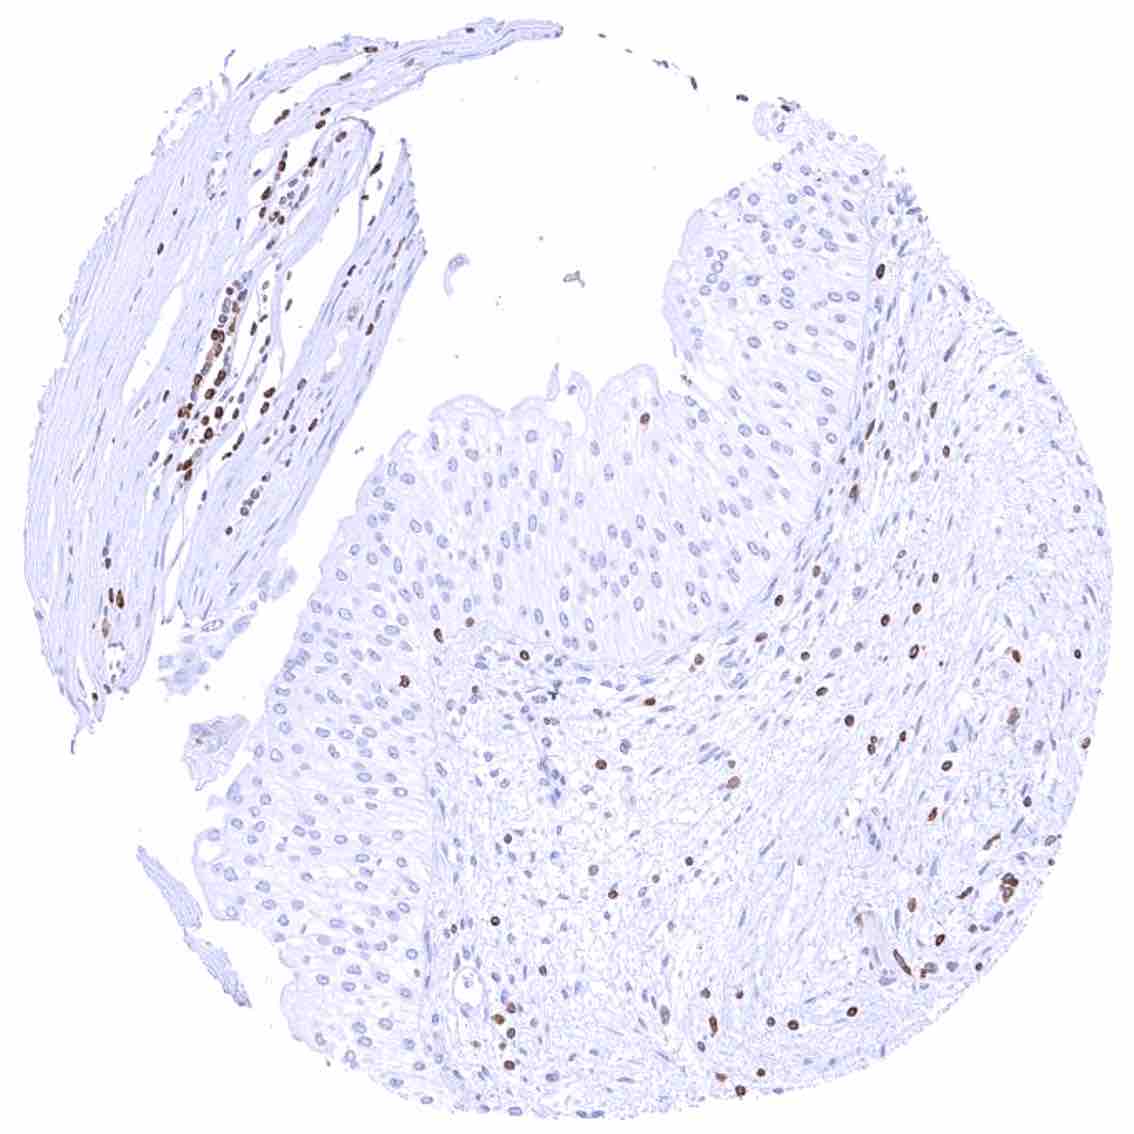

Uterus, ectocervix – Strong cytoplasmic bcl-2 staining of basal cells of the squamous epithelium in this sample.